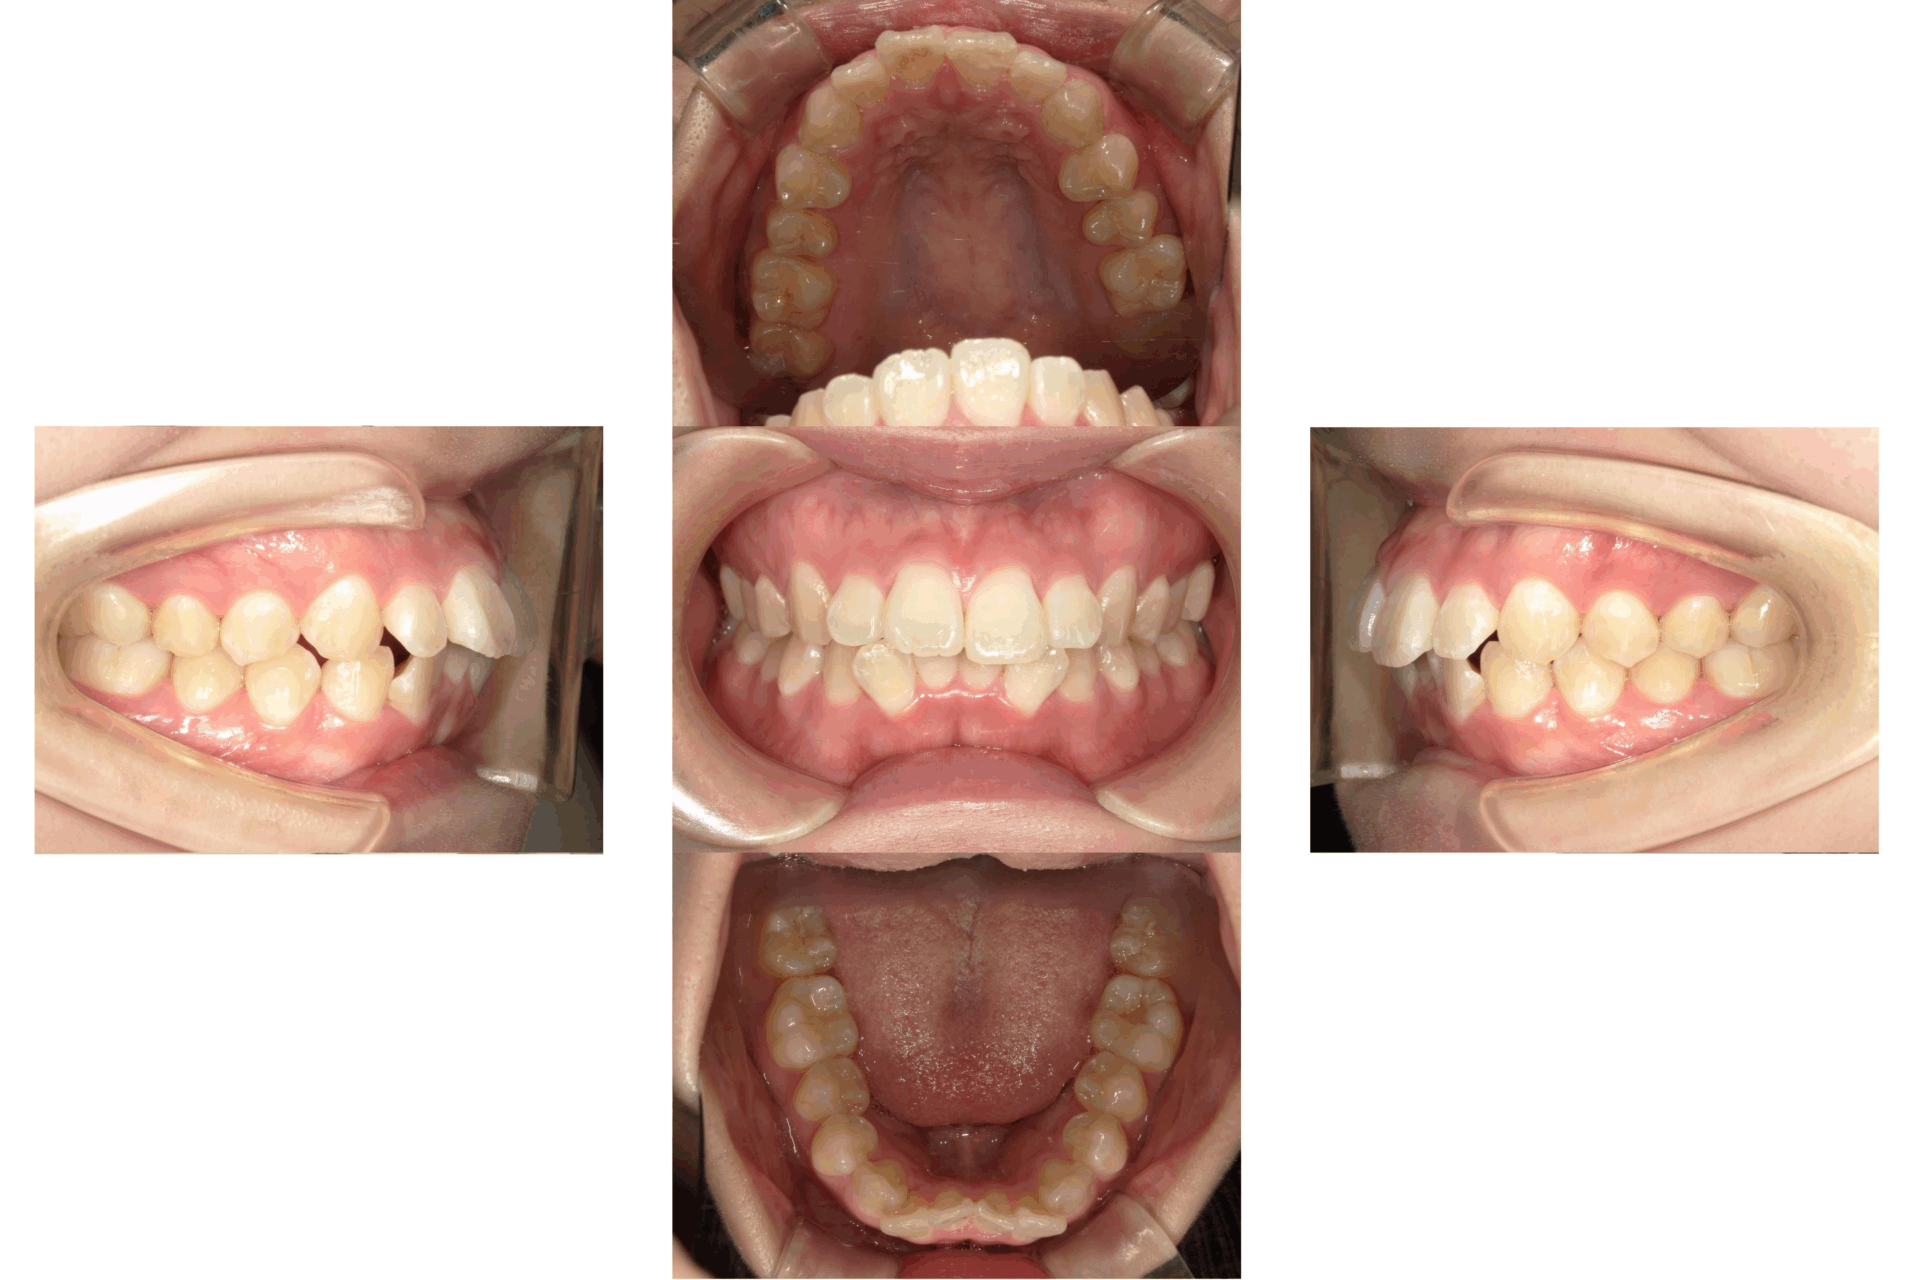

10代、女性、ワイヤー

| 施術内容 | 主訴:上下前歯でこぼこ。なるべく抜きたくない。 詳細:ワイヤー矯正での歯並び改善 詳細:ワイヤー矯正での歯並び改善 歯肉炎リスクあるため、今後は後戻りのチェックとともに歯肉炎管理もしていきます。 |

| 治療期間 | 12ヶ月(2/6現在 治療終了) |

| リスク・副作用 | ■リスク・副作用 ・治療の初期段階では、痛みや不快感が生じやすくなりますが、一週間前後で慣れます。 ・歯の動き方には個人差があるため、予想された治療期間より延長する場合があります。 |

| 費用 | ワイヤー矯正 60万円(税込660,000円) |